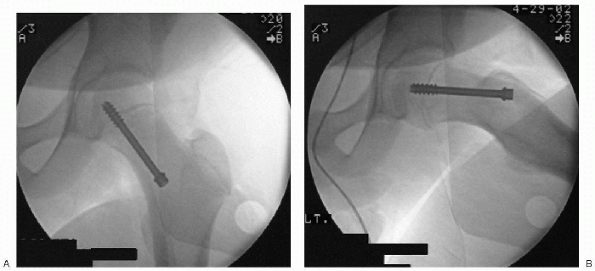

reduction can be accomplished with a single cannulated screw or pin and

is considered the gold standard. The screw or pin should enter the

anterior aspect of the proximal femur, cross the physis at 90 degrees,

and enter the center of the epiphysis with the tip below subchondral

bone. A screw placed in this orientation accommodates the deformity,

and has maximal stability with minimal risk of complications (Fig. 11-6).

![]() |

Figure 11-6 Operative anteroposterior (A) and frog-leg (B) radiographs showing single screw fixation.